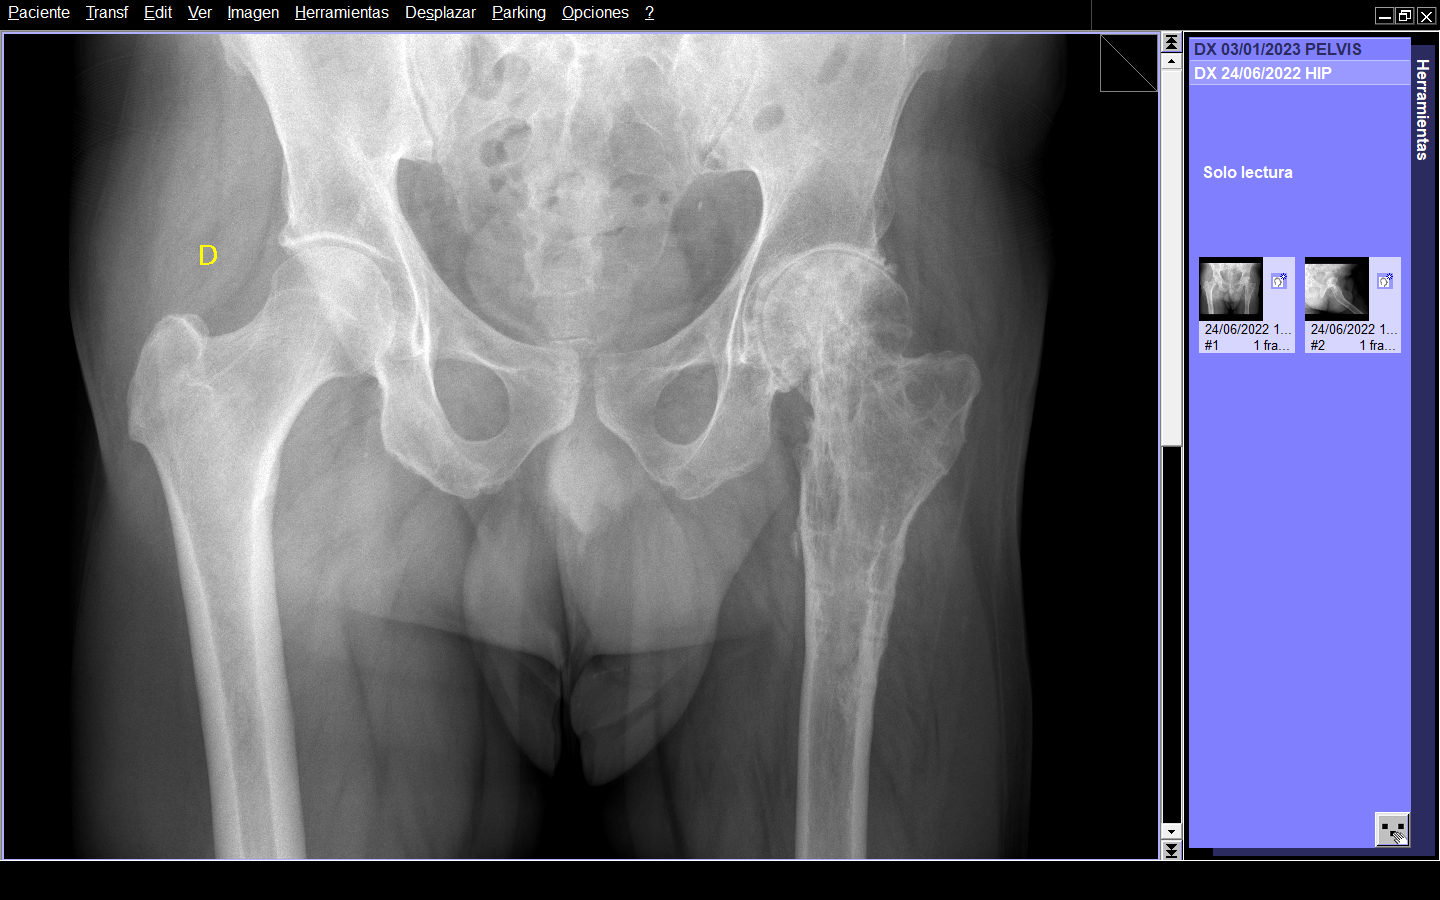

Paciente masculino de 57 años con antecedente de accidente de motocicleta en 1983, tras lo cual sostuvo fractura-luxación de cadera izquierda, tratada mediante reducción abierta y osteosíntesis de fémur proximal. Refiere que fue sometido a múltiples procedimientos quirúrgicos, siendo el último el retiro del material de osteosíntesis. Acude a consulta por dolor inguinal izquierdo de más de un año de evolución, utilizando apoyo para la deambulación (muletas). A la exploración física, no hay dismetría de extremidades inferiores, presenta rotación interna y externa de cadera izquierda abolidas. Asimismo, en reposo, el miembro inferior izquierdo mantiene actitud en flexión de 10°.

Radiográficamente, en AP presentaba deformidad en fémur proximal izquierdo de 160º en valgo, disminución del espacio articular, geodas en cabeza femoral. En la radiografía lateral se observaba curvatura en la metáfisis femoral con ápex posterior de 27º. (Figura 1 y 2)

Figura 1. Radiografía AP de ambas caderas.